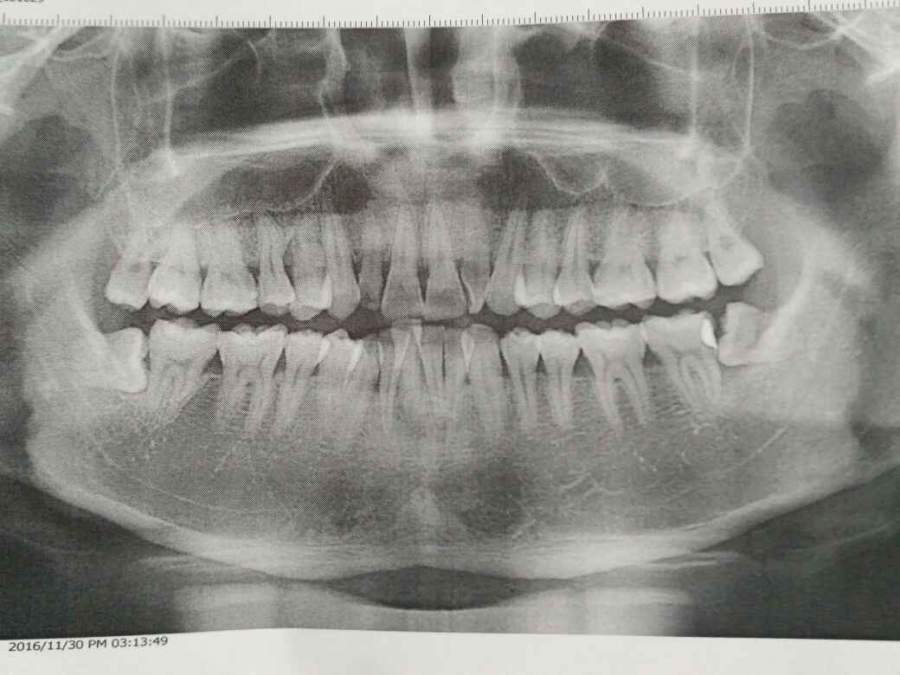

ÇëÎÊÕâËÄ¿ÅÖdzݶ¼Òª°ÎÁËÂ𣬱¾À´ÊÇÏëÖ»°ÎÏÂÃæÄÇÁ½¿ÅµÄ ·¢×ÔСľ³æAndroid¿Í»§¶Ë |